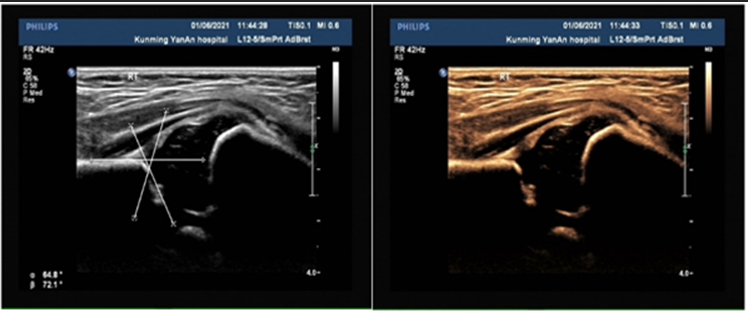

正常小儿髋关节超声图像

小儿髋关节脱位超声图像

(内收屈曲位股骨头大部分位于髋臼外)